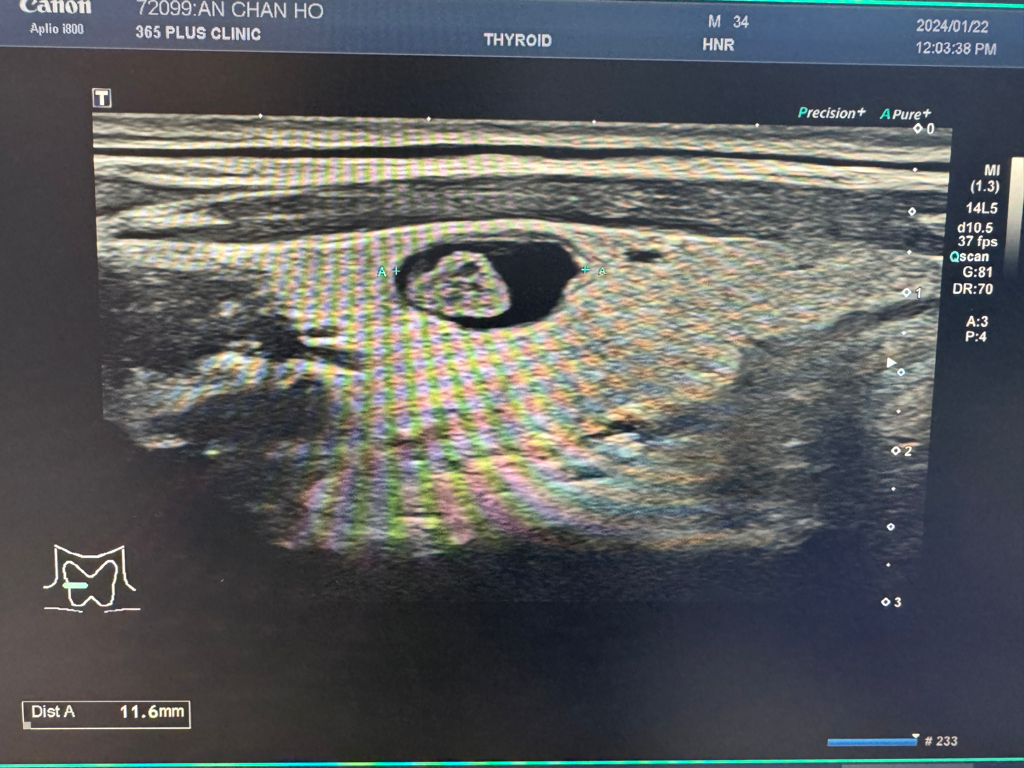

해당 병변은 낭성 결절에 고형 portion 이 함께 관찰되는 양상의 결절이며 악성이 의심되는 소견은 따로 보이기 때문에 KTIRAD 분류상 3정도 (Low suspicion) 에 해당하고 6~1년 간격의 경과관찰이 가능할 것으로 판단됩니다.